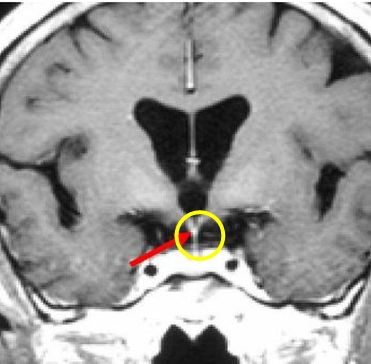

Bệnh nhân Nguyễn V. G., nam, 59 tuổi. Bệnh nhân vào viện vì đau đầu, đái nhiều và mệt mỏi, khám tại Trung tâm Y học hạt nhân và Ung bướu - Bệnh viện Bạch Mai và được chẩn đoán: U sọ hầu. Bệnh nhân được chỉ định điều trị xạ phẫu bằng dao gamma quay, liều 12Gy. Sau điều trị 18 tháng bệnh nhân về mặt lâm sàng cải thiện nhiều. Khối u tan biến hoàn toàn.

Hình ảnh MRI sọ não. Trước điều trị (hình bên trái): khối u sọ hầu (vòng tròn xanh). Sau điều trị 18 tháng (hình bên phải): khối u tan hết.